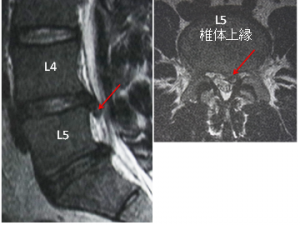

図10-③.術後1年 ヘルニアはなく、腰下肢痛もありません。